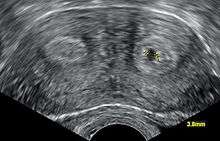

It is possible to diagnose a bicornuate uterus using gynecologic ultrasonography,[1] specifically sonohysterography, and MRI.[2] However, as there is no indication to do such procedures on asymptomatic women, the presence of a bicornuate uterus may not be detected until pregnancy or delivery. In a C-section (usually done due to malpresentation), the irregular shape of the uterus will be apparent.